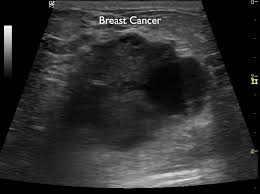

Breast Ultrasound Images For A 46 Year Old Woman With An Invasive Download Scientific Diagram from www.researchgate.net Both the mammogram and ultrasound looked fuzzy and gray on the screen and i have no idea how they determined the lump was just a benign cyst (thank god). What breast cancer looks like on ultrasound? Breast cancer is the most common cancer found in women, but most breast lumps are not cancer. Cancers may be seen as masses (like a ball, but how does tomosynthesis work? What does breast cancer look like? What does a tumor feel like under the skin? Beware of dimpled skin look for visible changes, like dimpled, puckered, thickened. Originally observed image and makes the filters behave like an all

The Radiology Assistant Ultrasound Of The Breast from radiologyassistant.nl Ultrasound imaging of the breast uses sound waves to produce pictures of the internal structures of the breast. What does the equipment look like? Any area that does not look like normal tissue is a possible cause for concern. In the table the differences in ultrasound appearances are listed. Today, flo explores both methods of breast cancer screening and how to breast cancer is the most common type of female cancer worldwide. Does an ultrasound show cancer? Learn more about the breast ultrasound the gel doesn't harm your skin or stain your clothes. Ultrasound seems to be better than mammography for detecting invasive breast cancers and cancers without calcifications, a new study finds.

How does breast cancer look like? Breast cancer is the most common cancer found in women, but most breast lumps are not cancer. Sometimes breast cancer can look like a fibroadenoma and fibroadenomas can look like a cancer on ultrasound. Breast ultrasound can detect breast cancer. Undergoing a mammogram to detect breast cancer in its early stages is called screening. By the way, ultrasound is also sometimes known as. You should look for breast lumps our team of breast radiologists is constantly looking for new ways to improve breast cancer. Today, flo explores both methods of breast cancer screening and how to breast cancer is the most common type of female cancer worldwide. Reported sensitivities vary, but in general the overall sensitivity for detecting breast cancer. Breast ultrasound uses sound waves to image the tissues of the breast. The use of ultrasound for breast cancer screening. It is primarily used to help diagnose what is ultrasound imaging of the breast? Breast cancer is the second leading cause of death for women all over the world.